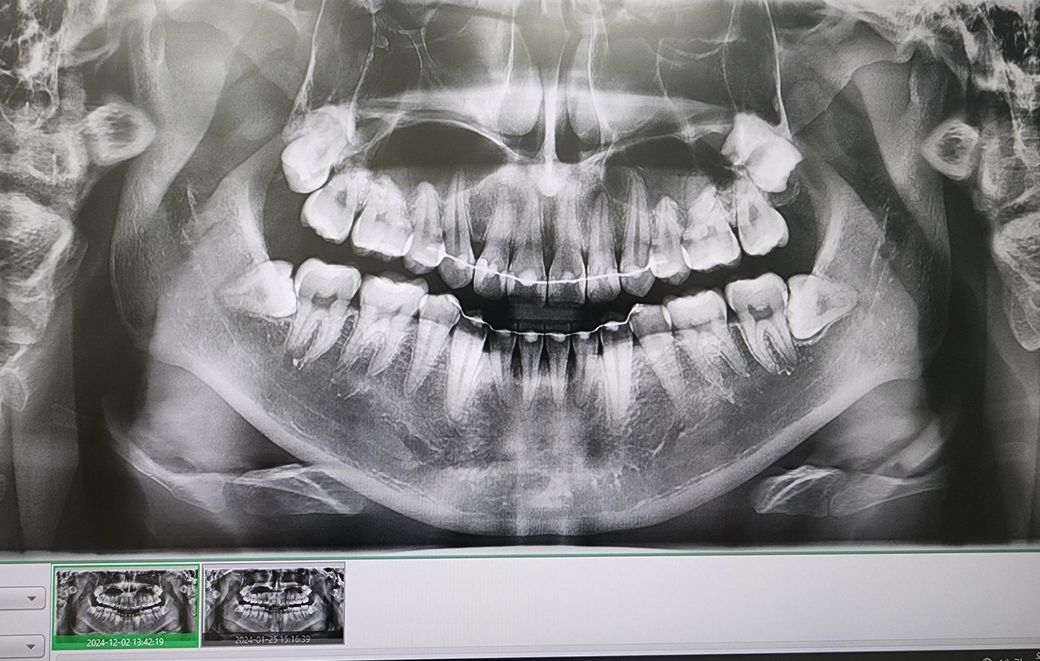

치과의사분들 파노라마 사진 해석부탁드립니다

사진상 앞니 오른쪽 뿌리끝에 작은 염증이 있다고 합니다

사진은 24년1월 24년 12월 25년 5월 순입니다

염증이 커지는 상황일까요?

아픈곳이나 시린곳은 없습니다 치료해야된다고 보시나요

엑스레이 상으로는 크게 염증이 커지거나 그렇진 않은거 같습니다. 증상이 없다면 정기적으로 치과를 다니시면서 관리를 받으시면될것같습니다.

사진상으로는 염증이 명백히 보이지만 증상이 없다면 일단 지켜보는 것도 괜찮을 것 같습니다.

파노라마 사진상으로 측은단 부위에 병소가 보이고 있습니다. 정확한 확인을 위해서는 CT 촬영을 해보는 것이 좋을 것으로 생각되며 치근단 질환이 생겼다는 것은 근관 내가 이미 감염이 되었다는 것이기 때문에 치근단 질환이 있다면 신경 치료를 해줘야 합니다. 그렇지 않다면 주변에 있는 치조골이 손상되어 나중에는 치아를 손실 할 수도 있습니다.